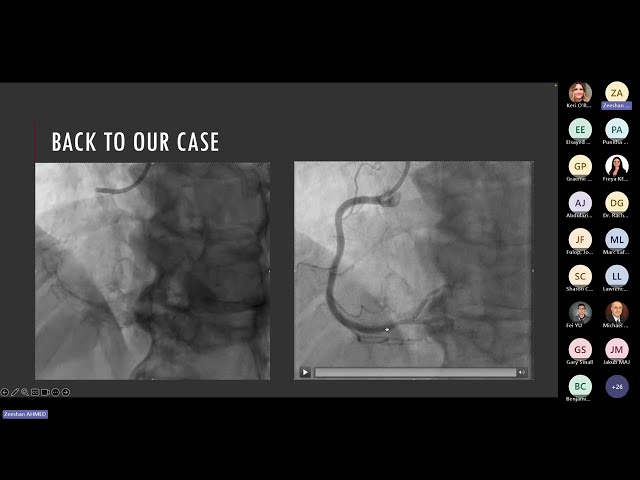

Watch this 54-minute cardiology rounds presentation where Dr. Zeeshan Ahmed from the University of Ottawa Heart Institute reviews key clinical trials presented at the European Society of Cardiology (ESC) 2025 conference. Gain insights into the latest cardiovascular research findings and their potential implications for clinical practice as Dr. Ahmed, who holds credentials in cardiology (FRCPC, DRCPSC) and medical education (MHPE), breaks down significant trial results from one of cardiology's most important annual conferences. Learn about emerging evidence in cardiovascular medicine and how these new findings may influence future treatment approaches and patient care strategies.

Recap of (some) ESC 2025 Trials with Zeeshan Ahmed, MD